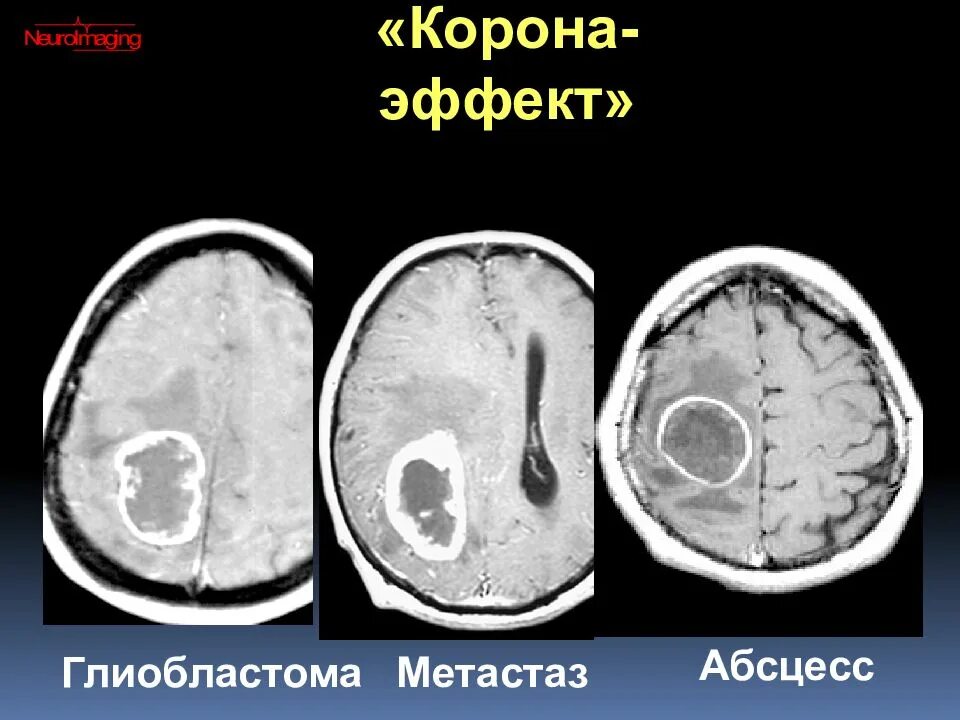

Метастазы головного мозга кт